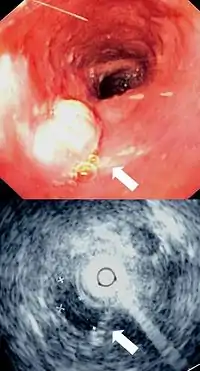

![]() صورة بالنتظير الباطني لمصاب بسرطانة غدية مريئية عند الوصلة المعدية المريئية. صورة بالنتظير الباطني لمصاب بسرطانة غدية مريئية عند الوصلة المعدية المريئية. | |

إن أفضل الطرق لتشخيص المرض هي عن طريق التنظير الباطن العلوي حيث يمكن رؤية الورم بشكل مباشر وأخذ خزعات من المناطق المصابة وفحصها مخبرياً، كما يمكن استخدام عدة فحوصات شعاعية للمساعدة في تشخيص المرض وتحديد مدى تغلغل الورم وانتشاره، من أهم تلك التقنيات: التصوير الطبقي المحوري و وجبة الباريوم, وقد يتم إجراء اختبار حركية المريء لاستبيان تضرر عضلات المريء بسبب السرطان.